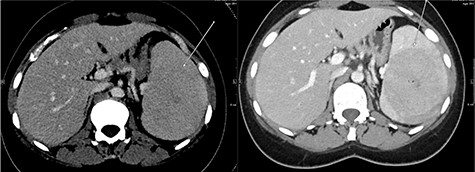

Abdominal ultrasonography showed a 5.0 × 5.0 cm well-defined, rounded, lobulated and hypoechoic vascular solid splenic lesion with no increased transmission or calcification. This lesion had vessels radiating from the center to the periphery (Fig. 1). Further evaluation with contrast-enhanced computed tomography (CT) of the abdomen showed a 6.0 × 5.6 × 4.4 cm solitary, rounded and lobulated non-calcified mass in the spleen, demonstrating heterogeneous, linear and nodular arterial enhancement with progressive filling in the portal venous and delayed phases (Fig. 2).

Ultrasound images with Doppler showing a well-defined rounded hypoechoic mass with vascularity in the peripheral areas as well as inside the lesion with no through transmission.